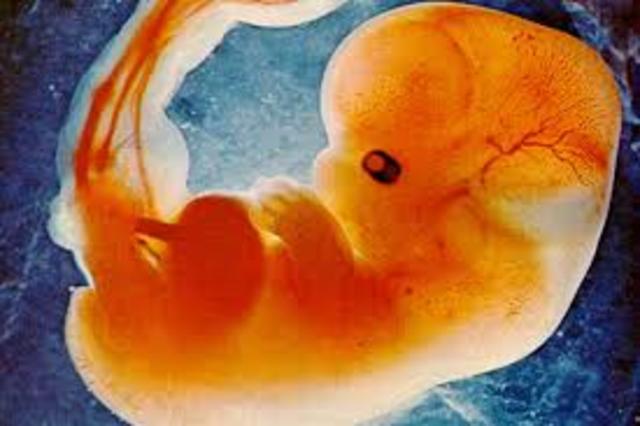

• Period of embryo

Period of embryo

3-8 weeks the umbilical cord extends from the embryo and connects to the placenta.The egg is fertilized. The amniotic fluid is beginning to collect around the ball of cells in the cavity that will become the amino sac.